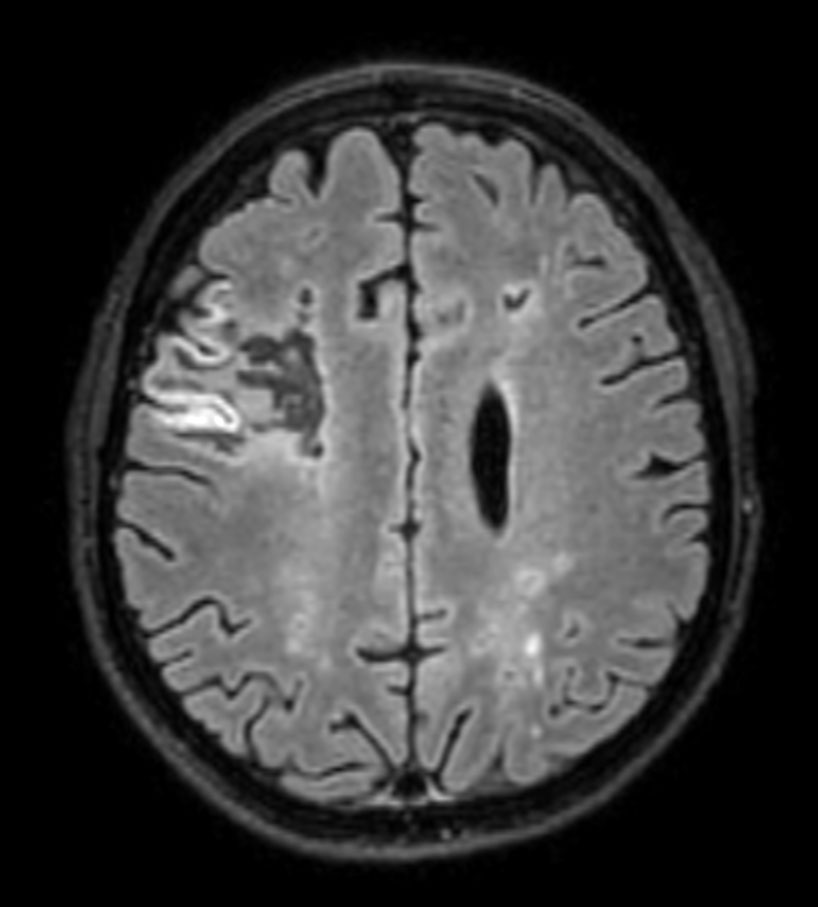

3D T2w FLAIR Compressed SENSE

-

3D T2w FLAIR (reformat) Compressed SENSE